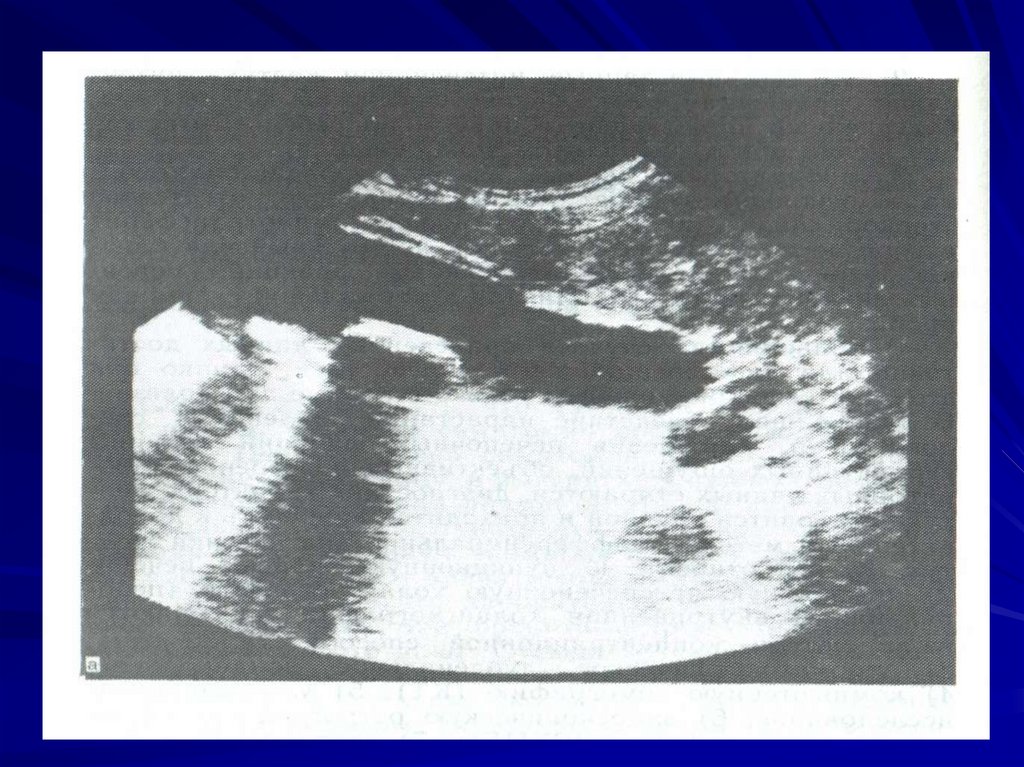

38. Данные УЗИ

Ультразвуковыми признаками катарального

холецистита являются:

увеличение размеров желчного пузыря,

утолщение его стенок до 4-5 мм, которые на

всем протяжении имеют ровные, четкие

контуры. Кроме того, отсутствуют

структурные изменения в прилежащих к

желчному пузырю тканях.

39.

Достоверными признаками деструктивного

холецистита

служат увеличение размеров желчного

пузыря (более 90,0 х 30,0 мм), значительное

утолщение стенок (6 мм и более), удвоение

(расслоение) стенки, неровность контуров и

наличие взвешенных мелких гиперструктур

без акустической тени в полости желчного

пузыря (гной).

Помимо этого выявляются жидкость в

подпеченочном пространстве и зоны

повышенной эхогенности окружающих

тканей - признаки воспалительной

инфильтрации.